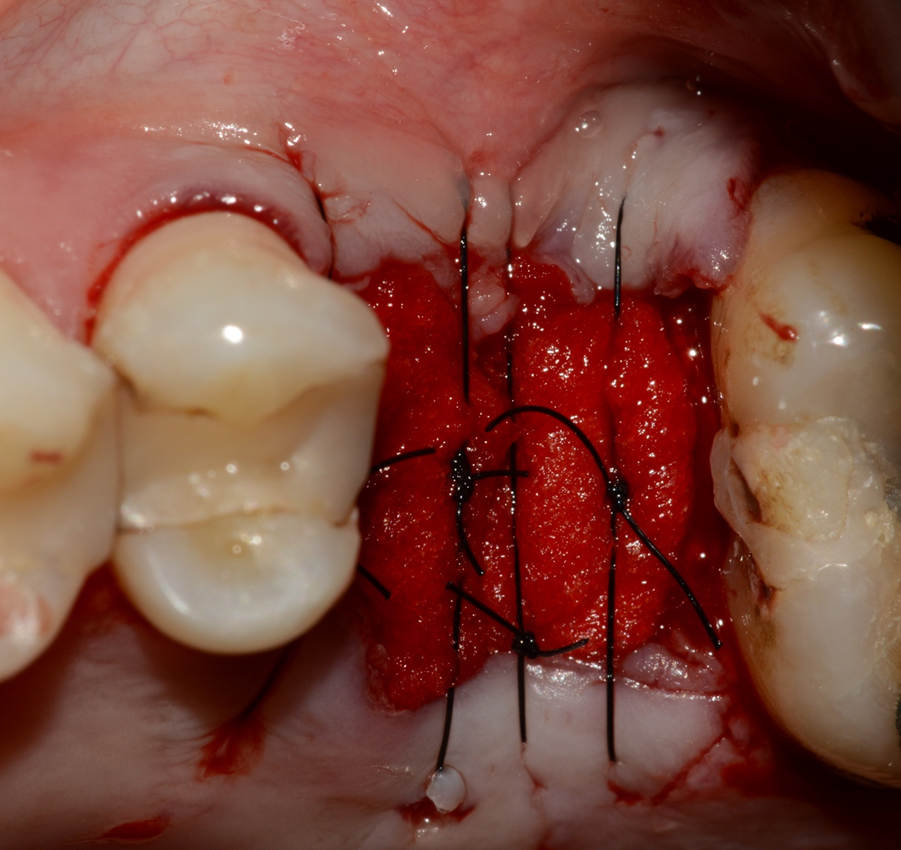

Estudos comprovaram que o preenchimento do alvéolo com um substituto ósseo (xenógeno ou sintético) com propriedades osteocondutoras auxilia no processo de regeneração e aumenta a neoformação óssea. Por isso, hoje a abordagem para exodontia é, sempre que possível, preencher o alvéolo. No caso da instalação de implante imediato, a indicação é a mesma: preencher os gapsentre implante e tecido ósseo e/ou alvéolos radiculares com o substituo ósseo.

O Extra Graft é um biomaterial muito interessante para aplicação nestes casos, pois apresenta-se na forma de blocos fracionados (0,5g / 1g / 2g) e tem em sua composição 75% de hidroxiapatita (principal componente mineral do osso) e 25% de colágeno do tipo I (proteína mais abundante na porção orgânica do osso) – ambos de origem bovina. Devido a essa composição, possui grande atividade osteocondutora e maior adesão dos osteoblastos, aumentando a velocidade de neoformação óssea. Além disso, a porção de colágeno gera maior estabilidade do coágulo e ação hemostática, promovendo menor sangramento pós operatório e maior conforto ao paciente. O Extra Grafté de fácil manuseio e condensação dentro dos alvéolos e é radiopaco, facilitando a conferência do preenchimento via radiografia final do procedimento.

A sequência de imagens a seguir apresenta casos da aplicação clínica do Extra Graft em cirurgias de exodontia e implante imediato com preenchimento dos gaps, e apenas exodontia e preenchimento alveolar para favorecer a regeneração óssea.